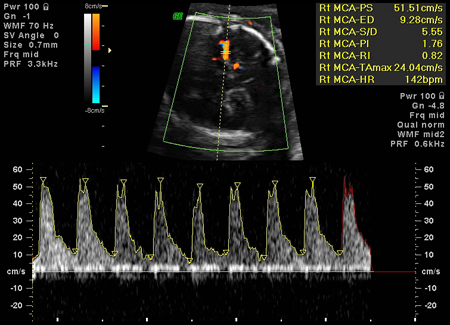

Velocimetría Doppler de la arteria cerebral media fetal (velocidad sistólica pico)

Prueba

La ecografía Doppler medida con una estimación de la velocidad sistólica máxima en la ACM fetal se puede utilizar para predecir la anemia moderada a grave en el feto. La velocidad sistémica máxima de ACM aumenta en los fetos con anemia significativa. Una alta velocidad del flujo sanguíneo para la edad gestacional debería dar lugar a la toma de muestras de sangre percutáneas del cordón umbilical (si hay una fuerte sospecha de anemia).[37][Figure caption and citation for the preceding image starts]: Aumento de la velocidad en la arteria cerebral media, coherente con anemia fetal graveOttawa Hospital; utilizado con el consentimiento de la paciente [Citation ends].

Resultado

≥1.5 MoM